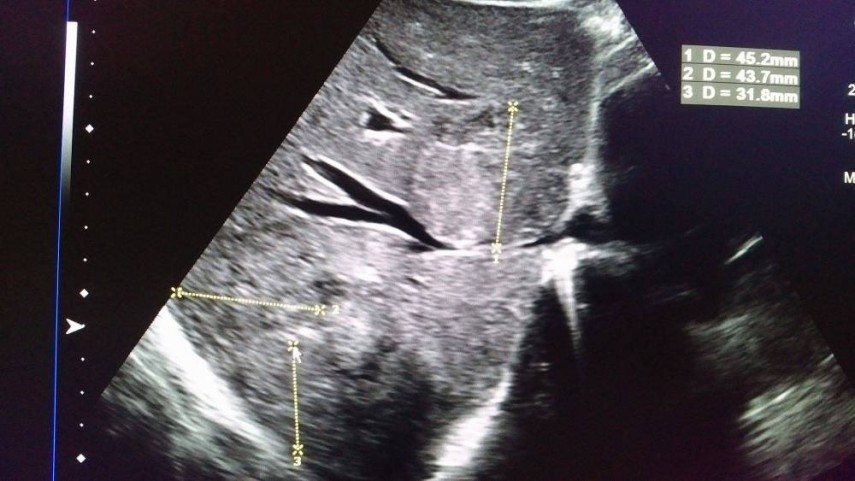

Gandul mi-a zburat apoi si la alti pacienti evaluati in ultima luna, la un prieten de 59 ani suferind tot de aceasta boala teribila,la tatal unei prietene de familie ce s-a prapadit de curand,dar si la cei bolnavi de inima-la unul din pacienti ce se va opera pe 1 februarie intr-o incercare de a repara valva mitrala-poze mai sus.Parca nici valvele cardiace nu mai rezista vremurilor.Dupa amiaza aceasta am trimis un barbat de 43 ani la angioplastie…prea multi tineri.